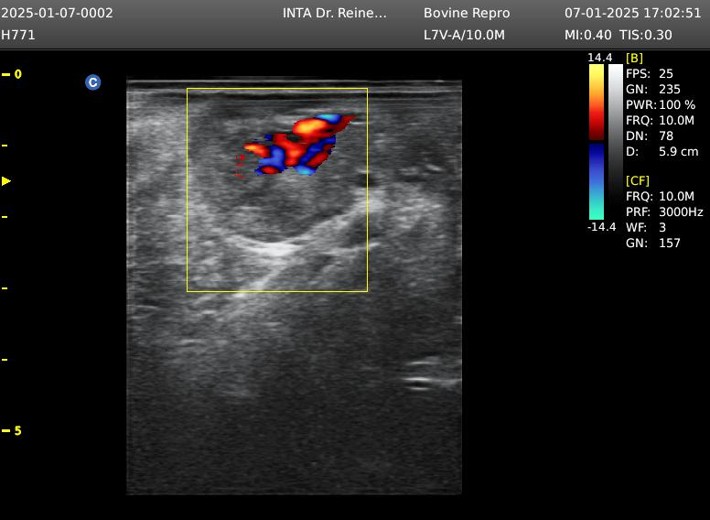

Generalmente, en rodeos comerciales, el diagnóstico del estado gestacional puede realizarse con precisión y de forma práctica a partir del día 30 posterior a la inseminación artificial, mediante la observación directa de la presencia o ausencia de líquido amniótico y del embrión en los cuernos uterinos. Más recientemente, se ha propuesto un método indirecto, utilizando ultrasonografía color, basado en la vascularización del cuerpo lúteo.

El cuerpo lúteo es una estructura ovárica encargada de sintetizar y liberar progesterona, hormona encargada de mantener la gestación. El equipo de profesionales del INTA Santiago del Estero y otros grupos de investigación, en otros trabajos ya publicados, describen que la disminución del flujo sanguíneo en el cuerpo lúteo podría indicar la aparición de luteólisis, relacionada con la ausencia de un embrión en el útero y, en consecuencia, la activación de vías apoptóticas que disminuyen la biosíntesis de progesterona. Por el contrario, una asociación positiva entre el flujo sanguíneo en el cuerpo lúteo y la concentración de progesterona es interpretada como un cuerpo lúteo activo.

Por lo tanto, la evaluación de la vascularización del cuerpo lúteo mediante ultrasonografía color puede considerarse una herramienta confiable para estimar la función lútea. Sin embargo, actualmente se utiliza un sistema de puntuación subjetivo para evaluar el área del tejido vascularizado y estimar la funcionalidad lútea, y hasta el momento no se habían desarrollado métodos objetivos, automatizados y rápidos, que relacionen la vascularización del cuerpo lúteo con el estado gestacional temprano, mediante estrategias de aprendizaje automático.